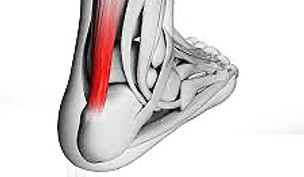

Tendinopathie calcanéenne

Motif de consultation :

Douleur à l’arrière du talon, gênant la marche ou les activités sportives, souvent liée à une surutilisation.

Objectif de la prise en charge :

Soulagement de la douleur, activation de la cicatrisation si cela est possible. Optimisation de la charge d’entraînement, et renforcement progressif du tendon.